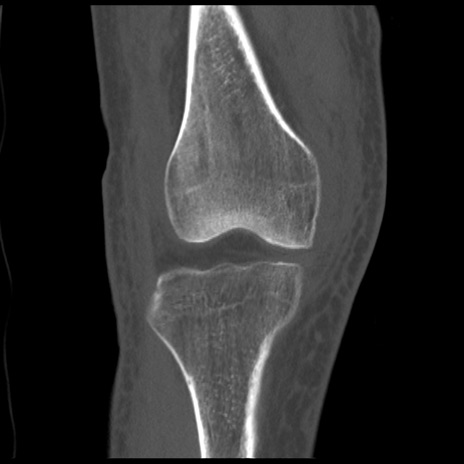

症例28 右膝関節CT(冠状断像)

右膝関節CT

矢状断像